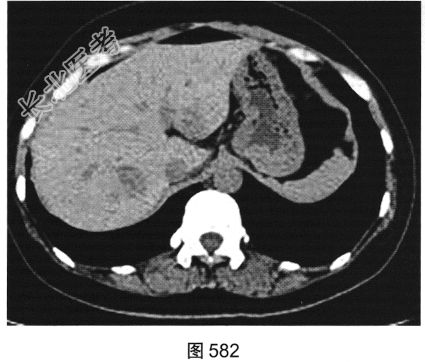

患者女性,38岁,因“间断性下腹部疼痛1周”入院。既往:否认肝炎、结核病史。查体:下腹部压痛。患者行腹部CT检查,见图582~图589。

- 多项选择题1.结合病史及影像学检查结果,可以考虑患者为以下哪些疾病( )

A、肝脏囊肿+附件囊腺瘤

B、肝脏转移瘤+附件囊腺癌

C、肝脏炎性假瘤+附件囊肿

D、肝脏炎性假瘤+输卵管积液

E、肝脏转移瘤+附件囊腺瘤

F、肝脏转移瘤+附件转移瘤